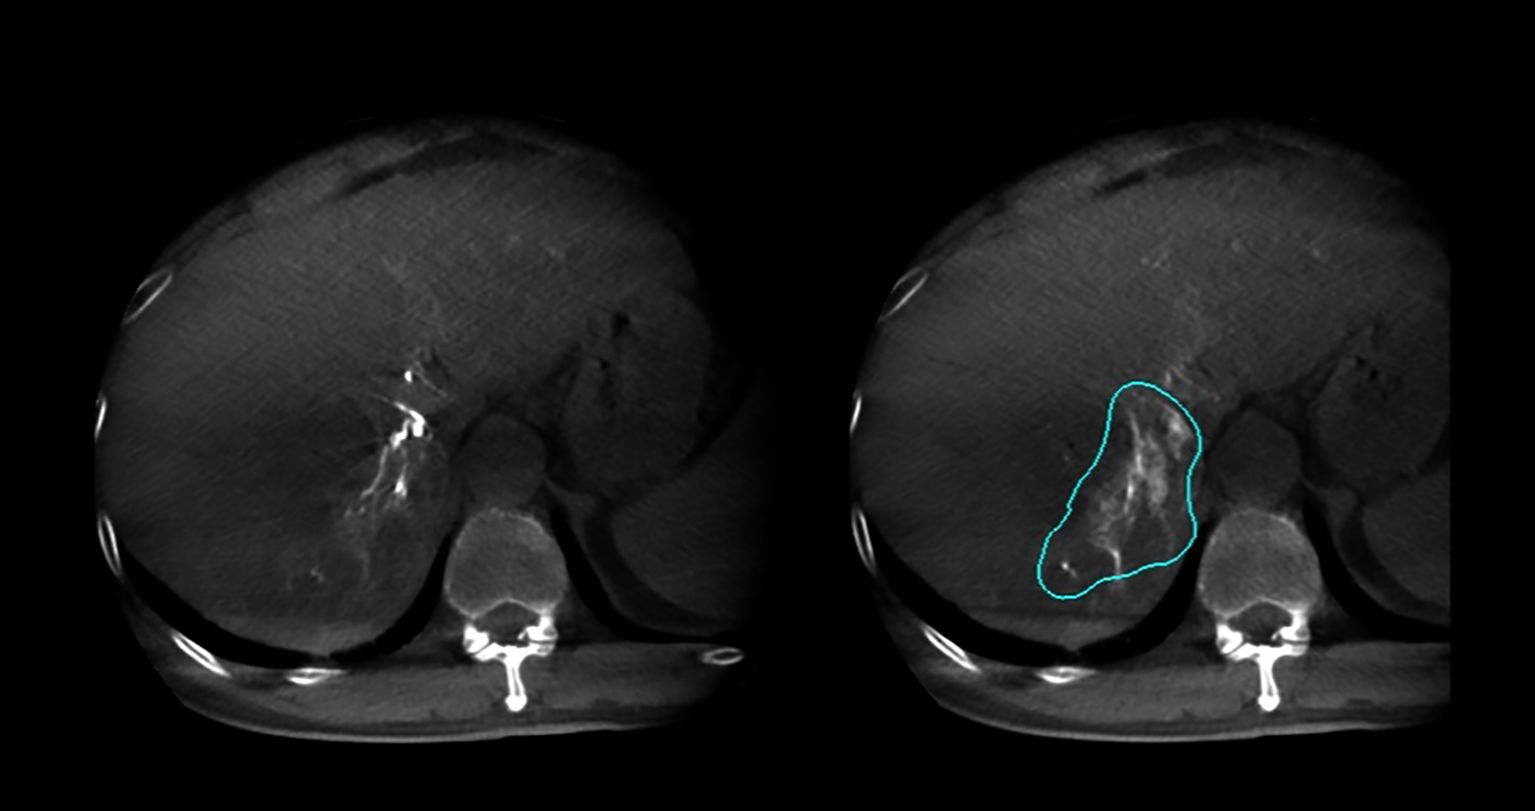

Figure 3

CT scan images showing axial views of a liver. The right image highlights a large liver tumor with a blue outline, while the left shows the tumor without the outline. Both images display the spine and surrounding organs in grayscale, with variations in tissue density.

Figure 3. Arterial phase and delayed phase contrast-enhanced dual CBCT images acquired after injection into the segmental right hepatic lobe. The perfusion area can be assessed based on the delayed phase image on the right.

In this study, 27 patients underwent liver DSA and dual CBCT scans prior to SIRT treatment to evaluate intrahepatic lesions, identify tumor-feeding vessels, ensure tumor enhancement, and exclude blood supply from collateral vessels. The Philips UNIQ FD20C (Philips Healthcare, Netherlands) was used. The dual CBCT was automatically triggered for image acquisition during the arterial and delayed phases. The flat panel detector rotated from -120° to +120°, enabling a comprehensive liver parenchyma scan. X-ray projections were acquired at 60 frames per second over 240°. The X-ray exposure was set to 120 kV, with a detector size of 48 cm and a pixel size of 4x4. Dual CBCT was performed during proper hepatic artery angiography by injecting 18 mL of contrast medium (Visipaque 320 mg I/ml) at a rate of 1.5 mL/s to evaluate total liver volume, right and left lobe volumes, and overall tumor burden. The first scan was initiated 4 seconds after the start of contrast injection, followed by a second scan commencing 8 seconds after the completion of the first, with each scan lasting 8 seconds. Subsequently, superselective DSA was conducted to assess the perfusion volume of specific hepatic arterial branches and the corresponding tumor volumes. For these injections, the contrast infusion rate was typically set at one-tenth of that used for conventional angiography. The total injection duration was defined as the time required for parenchymal opacification plus the rotation time of the imaging system, thereby ensuring that image acquisition occurred when the tumor region and its feeding arteries reached peak contrast enhancement. The total contrast volume administered was calculated as the product of the selected injection rate and injection duration. Contrast-enhanced dual CBCT data allowed precise measurement of the target liver lobe volume and tumor burden via a 3D segmentation tool. Arterial and delayed phase CBCT images enabled tumor area assessment, particularly during the delayed phase image (Figure 2). Injection into the segmental right hepatic artery provided detailed tumor perfusion area assessment. Both arterial and delayed phase images, especially the delayed phase (Figure 3), offered precise information on tumor perfusion.